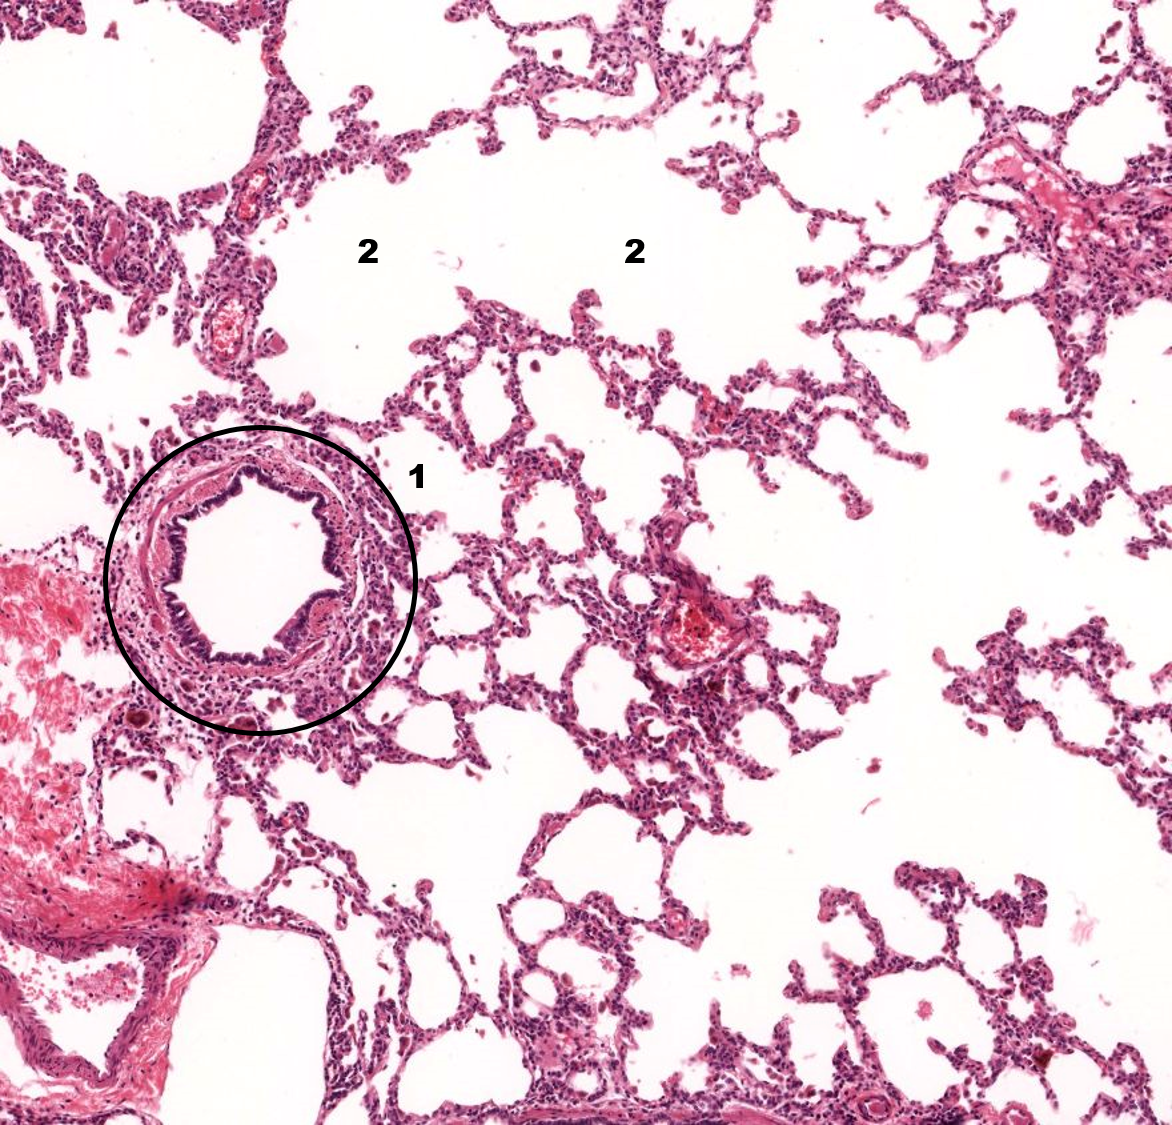

1: Alvéolo

2: Ducto alveolar